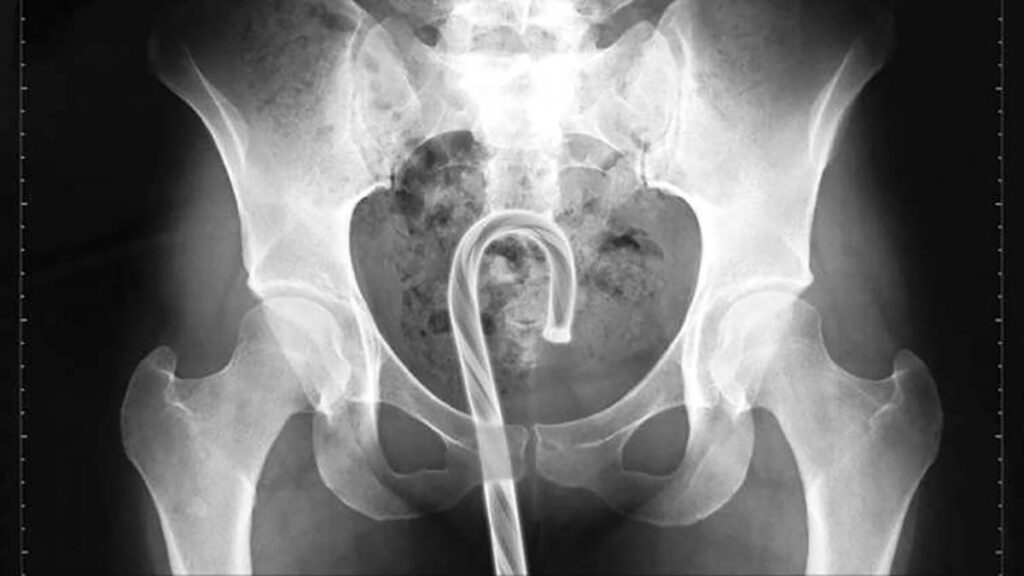

Gevolgd door een stevig hogere “iewww factor”

| Penis | Vagina | Anus |

|---|---|---|

| Schroefje | Geurzeep | Golfbal |

| Scherp speelgoed | Dop van deadorantbus | Pindakaas pot |

| 10 CM lang metalen seks speeltje | Meerdere tampons | Spuitbus |

| Plastic lepel | Flesdop | Gordijnroede |

| Dominosteentje | Penisring met spikes | Speelgoed |

| Onderdeel van een shampofles | Verroest metaal | Tandenborstel |

| Paperclip | Siliconen balletjes | Tandenborstel houder |

| Coaxkabel | Bal | Doosje flosdraad |

| Fiets reflector | Fles mondwater | |

| Anticonceptiespons tijdens menstruatie | Drinkglas | |

| Koptelefoontjes (oordopjes) | Schroevendraaier | |

| Hot Towel | Plastic vork | |

| Telefoon EN (munt)geld | Speelgoed raket | |

| Klei | Dildo EN brievenopener | |

| Kandelaar | Sigaarhouder | |

| Lolly | Mascarahouder in plastic zakje | |

| Balletje van een seksspeeltje | Tin Cup | |

| Haar borstel | ||

| Bus luchtverfrisser | ||

| Knikkers | ||

| Grote fles shampoo | ||

| Blikje kattenvoer | ||

| Zak kauwtabak | ||

| Flesje water | ||

| 3 AA Batterijen | ||

| 2 AAA Batterijen | ||

| D Batterij | ||

| Muntstuk (een maand lang) |